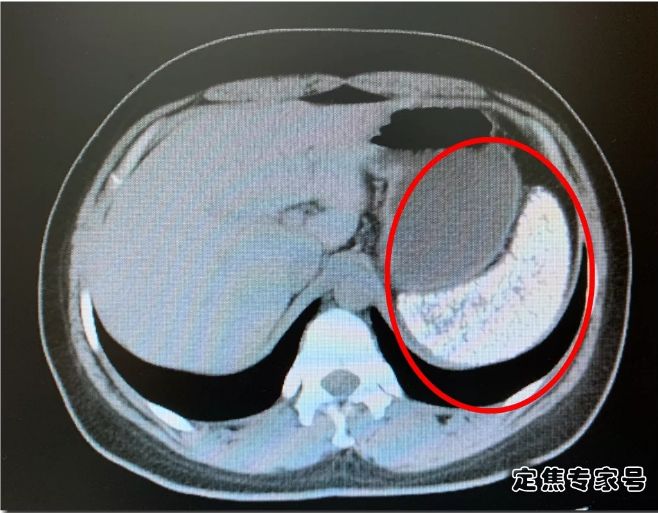

上面这就是何莉莉的CT片,图中发白的就是她的脾脏。我们知道CT成像,空心的是黑色的,完全实心的白色的。何莉莉的脾脏完全白色,也就意味着她的脾脏已经是一个实心大疙瘩,里面都是钙化点,几乎就是一块板砖了。

何莉莉CT片子出现的情况,李秉璐教授也是第一次见。既不是肿瘤,也不是感染,也不像是坏死,到底是怎么回事?只能手术的时候揭开谜底了。